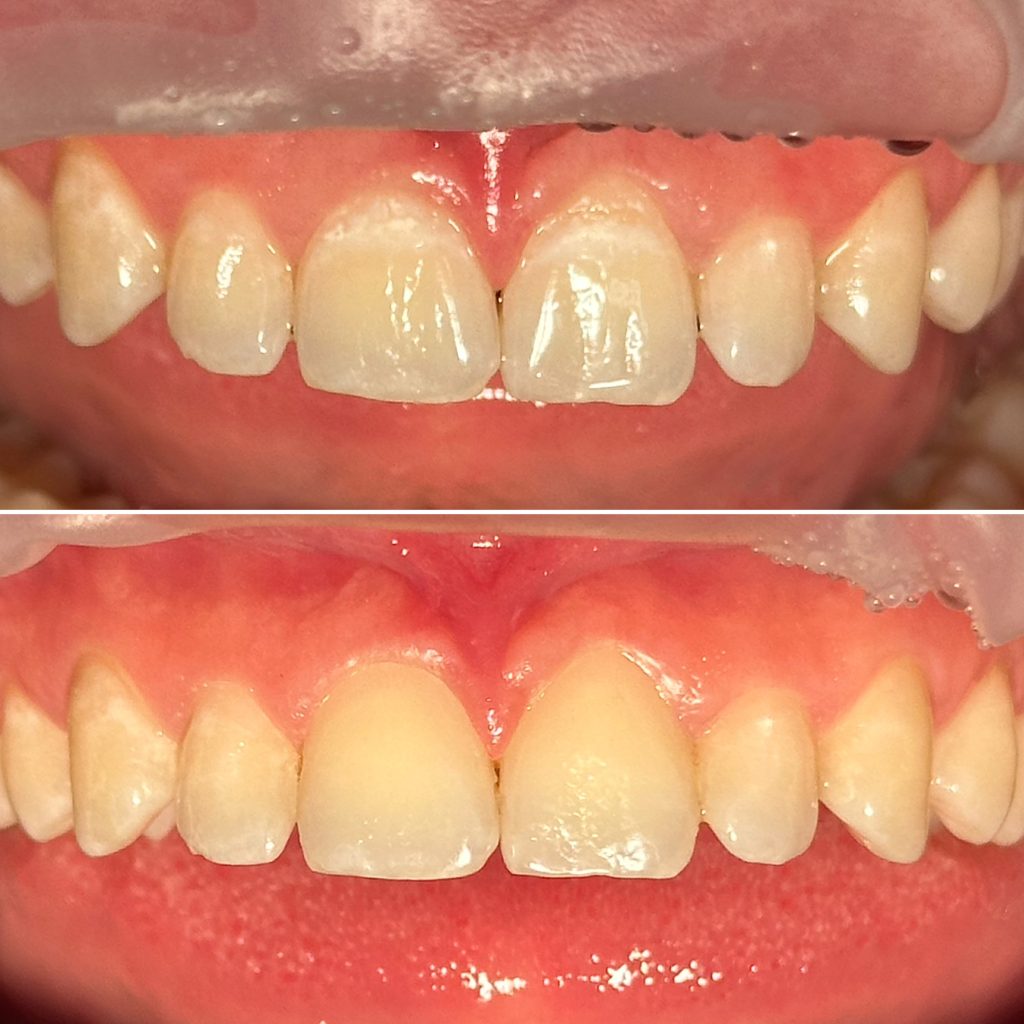

• Художественная реставрация фронтального и бокового участка зубов

2023 год – «Прямая композитная реставрация фронтальной группы зубов» Владимир Мальченко